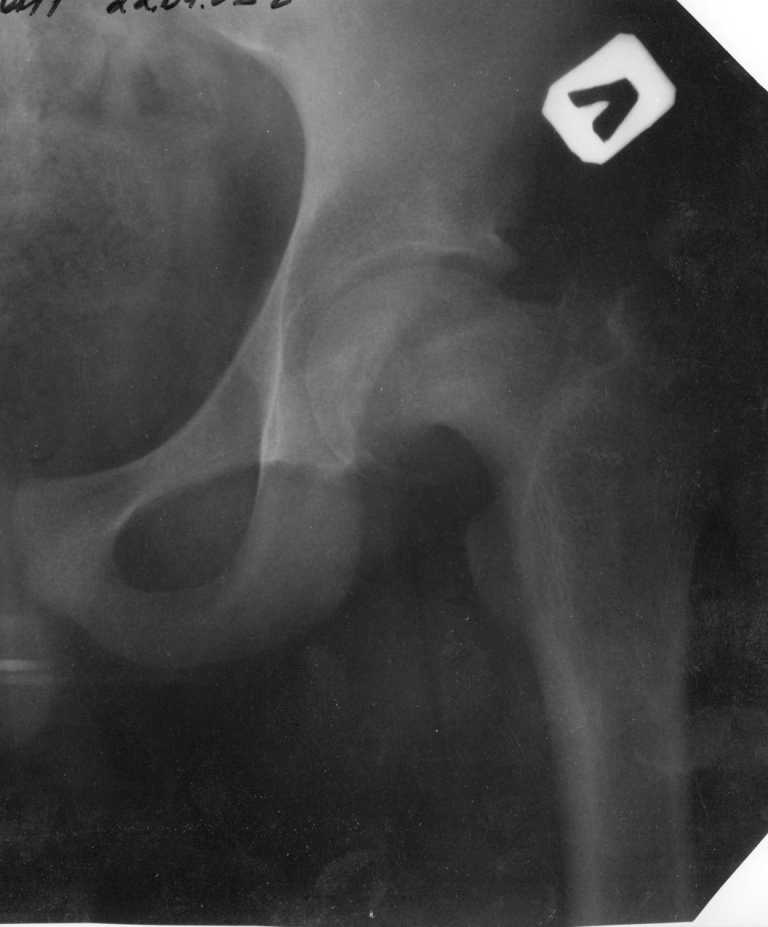

Необходим снимок второго сустава, потому что поражение может быть двухсторонним и, не исключено, что фиксировать надо оба сустава.

Второй сустав пока нормальный, но,каюсь, не прав, надо было не обрезать снимок. Исправлю.